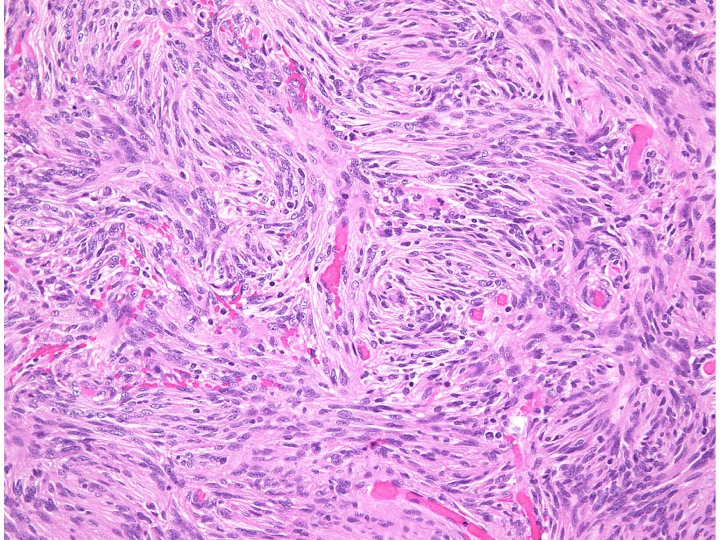

storiform pattern(長嶋和郎先生の病理教室)

紡錘形細胞が放射状に配列する所見でstoriform patten (花むしろ)、またはcartwheel (車輪)状に似た様子が見られます。軟部腫瘍であるfibrous histiocytomaで良く見られるものです。本例ではCP-angle meningiomaに見られた所見で、fibrous meningiomaの診断です。MIB-1 indexはやや高く8%でしたが、壊死や異型性は見られず、Grade 1相当とみなされます。HE x200

Fibrous meningiomaですが、渦巻状(whorl, long arrow) patternや玉ねぎ茎状 (onion bulb, short arrow) patternなどが見られます。HE x200